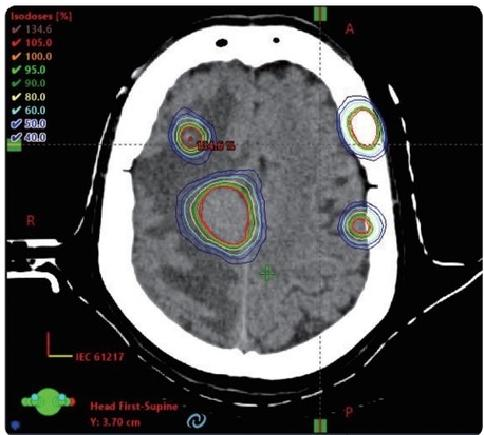

HyperArc technology

HyperArc is a non-coplanar stereotactic radiosurgery technology developed specifically for intracranial tumors. It has the characteristics of high precision, high efficiency and high automation. It has sub-millimeter accuracy and can complete the fixed-point radiosurgery treatment of several to dozens of brain metastases at the same time within 10 minutes, bringing better experience to patients with multiple brain me-tastases.

VMAT

HyperArc